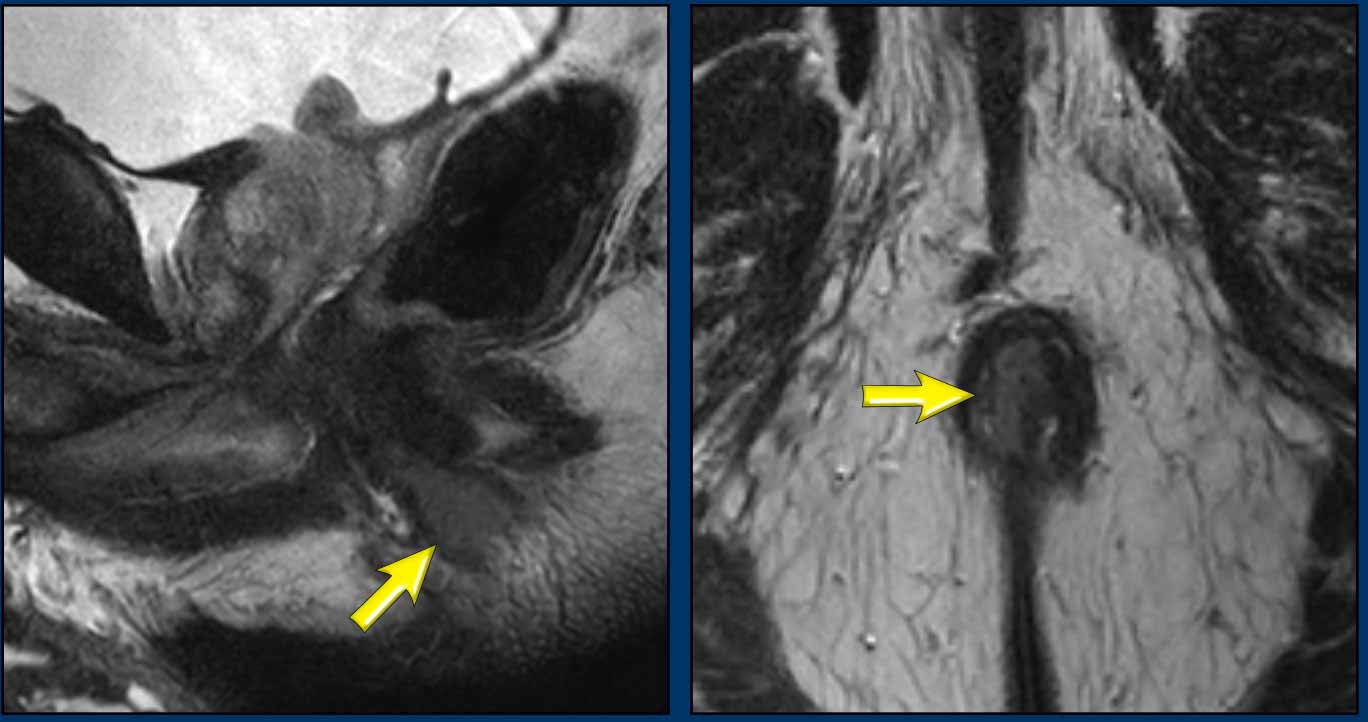

Image source : radiologyassistant.nl